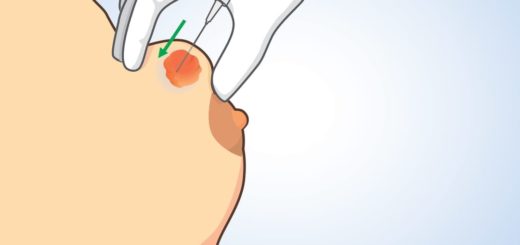

Vous ressentez une boule au niveau d’un de vos seins ? Il peut s’agir d’un nodule mammaire. Il s’agit d’une masse arrondie, circulaire, en cordon ou bref irrégulière que vous pouvez ressentir lors de...